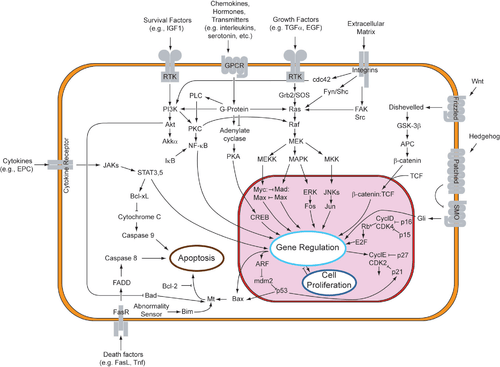

Because apoptosis cannot stop once it has begun, it is a highly regulated process. Apoptosis can be initiated through one of two pathways. In the intrinsic pathway the cell kills itself because it senses cell stress, while in the extrinsic pathway the cell kills itself because of signals from other cells. Both pathways induce cell death by activating caspases, which are proteases, or enzymes that degrade proteins. The two pathways both activate initiator caspases, which then activate executioner caspases, which then kill the cell by degrading proteins indiscriminately.

Activation mechanisms

The initiation of apoptosis is tightly regulated by activation mechanisms, because once apoptosis has begun, it inevitably leads to the death of the cell.[14] The two best-understood activation mechanisms are the intrinsic pathway (also called the mitochondrial pathway) and the extrinsic pathway.[15] The intrinsic pathway is activated by intracellular signals generated when cells are stressed and depends on the release of proteins from the intermembrane space of mitochondria.[16] The extrinsic pathway is activated by extracellular ligands binding to cell-surface death receptors, which leads to the formation of the death-inducing signaling complex (DISC).[17]

Before the actual process of cell death is precipitated by enzymes, apoptotic signals must cause regulatory proteins to initiate the apoptosis pathway. This step allows those signals to cause cell death, or the process to be stopped, should the cell no longer need to die. Several proteins are involved, but two main methods of regulation have been identified: the targeting of mitochondria functionality,[22] or directly transducing the signal via adaptor proteins to the apoptotic mechanisms. An extrinsic pathway for initiation identified in several toxin studies is an increase in calcium concentration within a cell caused by drug activity, which also can cause apoptosis via a calcium binding protease calpain.

Intrinsic pathway

The mitochondria are essential to multicellular life. Without them, a cell ceases to respire aerobically and quickly dies. This fact forms the basis for some apoptotic pathways. Apoptotic proteins that target mitochondria affect them in different ways. They may cause mitochondrial swelling through the formation of membrane pores, or they may increase the permeability of the mitochondrial membrane and cause apoptotic effectors to leak out.[18][23] They are very closely related to intrinsic pathway, and tumors arise more frequently through intrinsic pathway than the extrinsic pathway because of sensitivity.[24] There is also a growing body of evidence indicating that nitric oxide is able to induce apoptosis by helping to dissipate the membrane potential of mitochondria and therefore make it more permeable.[25] Nitric oxide has been implicated in initiating and inhibiting apoptosis through its possible action as a signal molecule of subsequent pathways that activate apoptosis.[26]

Mitochondrial proteins known as SMACs (second mitochondria-derived activator of caspases) are released into the cell's cytosol following the increase in permeability of the mitochondia membranes. SMAC binds to proteins that inhibit apoptosis (IAPs) thereby deactivating them, and preventing the IAPs from arresting the process and therefore allowing apoptosis to proceed. IAP also normally suppresses the activity of a group of cysteine proteases called caspases,[27] which carry out the degradation of the cell. Therefore, the actual degradation enzymes can be seen to be indirectly regulated by mitochondrial permeability.

Cytochrome c is also released from mitochondria due to formation of a channel, the mitochondrial apoptosis-induced channel (MAC), in the outer mitochondrial membrane,[28] and serves a regulatory function as it precedes morphological change associated with apoptosis.[18] Once cytochrome c is released it binds with Apoptotic protease activating factor – 1 (Apaf-1) and ATP, which then bind to pro-caspase-9 to create a protein complex known as an apoptosome. The apoptosome cleaves the pro-caspase to its active form of caspase-9, which in turn activates the effector caspase-3.

MAC (not to be confused with the Membrane Attack Complex formed by complement activation, also commonly denoted as MAC), also called "Mitochondrial Outer Membrane Permeabilization Pore" is regulated by various proteins, such as those encoded by the mammalian Bcl-2 family of anti-apoptopic genes, the homologs of the ced-9 gene found in C. elegans.[29][30] Bcl-2 proteins are able to promote or inhibit apoptosis by direct action on MAC/MOMPP. Bax and/or Bak form the pore, while Bcl-2, Bcl-xL or Mcl-1 inhibit its formation.

Extrinsic pathway

Two theories of the direct initiation of apoptotic mechanisms in mammals have been suggested: the TNF-induced (tumour necrosis factor) model and the Fas-Fas ligand-mediated model, both involving receptors of the TNF receptor (TNFR) family[31] coupled to extrinsic signals.

TNF-alpha is a cytokine produced mainly by activated macrophages, and is the major extrinsic mediator of apoptosis. Most cells in the human body have two receptors for TNF-alpha: TNFR1 and TNFR2. The binding of TNF-alpha to TNFR1 has been shown to initiate the pathway that leads to caspase activation via the intermediate membrane proteins TNF receptor-associated death domain (TRADD) and Fas-associated death domain protein (FADD). cIAP1/2 can inhibit TNF-α signaling by binding to TRAF2. FLIP inhibits the activation of caspase-8.[32] Binding of this receptor can also indirectly lead to the activation of transcription factors involved in cell survival and inflammatory responses.[33] However, signalling through TNFR1 might also induce apoptosis in a caspase-independent manner.[34] The link between TNF-alpha and apoptosis shows why an abnormal production of TNF-alpha plays a fundamental role in several human diseases, especially in autoimmune diseases.

The fas receptor First apoptosis signal (fas) – (also known as Apo-1 or CD95) binds the Fas ligand (FasL), a transmembrane protein part of the TNF family.[31] The interaction between Fas and FasL results in the formation of the death-inducing signaling complex (DISC), which contains the FADD, caspase-8 and caspase-10. In some types of cells (type I), processed caspase-8 directly activates other members of the caspase family, and triggers the execution of apoptosis of the cell. In other types of cells (type II), the Fas-DISC starts a feedback loop that spirals into increasing release of proapoptotic factors from mitochondria and the amplified activation of caspase-8.[35]

Common components

Following TNF-R1 and Fas activation in mammalian cells a balance between proapoptotic (BAX,[36] BID, BAK, or BAD) and anti-apoptotic (Bcl-Xl and Bcl-2) members of the Bcl-2 family is established. This balance is the proportion of proapoptotic homodimers that form in the outer-membrane of the mitochondrion. The proapoptotic homodimers are required to make the mitochondrial membrane permeable for the release of caspase activators such as cytochrome c and SMAC. Control of proapoptotic proteins under normal cell conditions of nonapoptotic cells is incompletely understood, but in general, Bax or Bak are activated by the activation of BH3-only proteins, part of the Bcl-2 family.

Caspases Caspases play the central role in the transduction of ER apoptotic signals. Caspases are proteins that are highly conserved, cysteine-dependent aspartate-specific proteases. There are two types of caspases: initiator caspases, caspase 2,8,9,10,11,12, and effector caspases, caspase 3,6,7. The activation of initiator caspases requires binding to specific oligomeric activator protein. Effector caspases are then activated by these active initiator caspases through proteolytic cleavage. The active effector caspases then proteolytically degrade a host of intracellular proteins to carry out the cell death program.